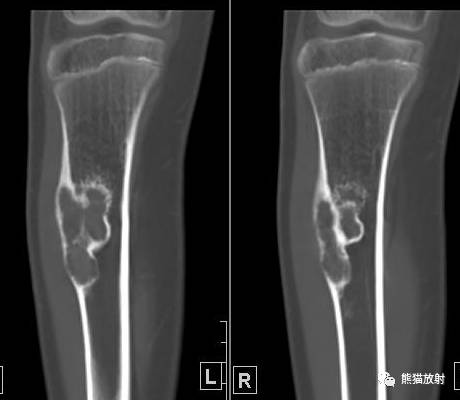

↓ 胫骨上端骨巨细胞瘤